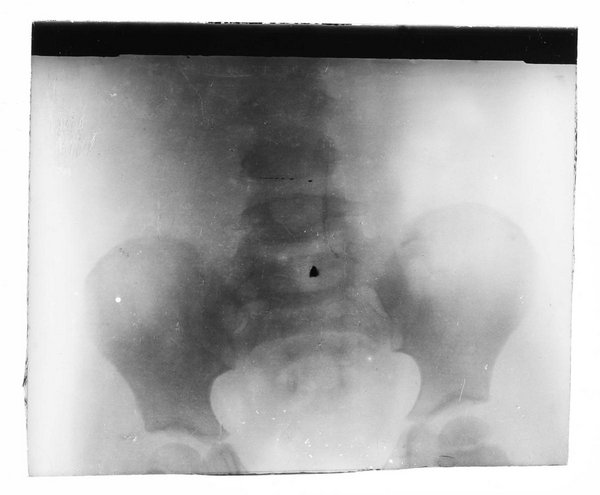

AT-MUW-FO-000101-0030

Medizinisches Fachgebiet

Radiologie

Objektart

Fotografie (FO)

Gegenstand

S/W, Glasdiapositiv

um 1896

Wien

Maße

Bildmaß 8,3 x 9,7 cm